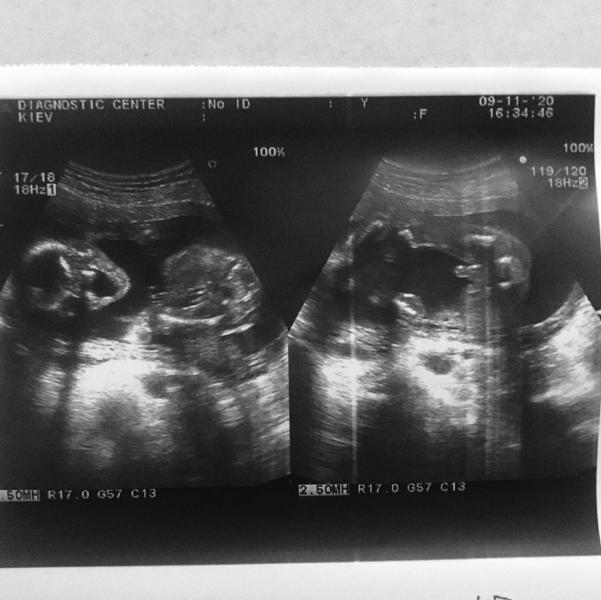

С малышом все замечательно! Попали на момент когда глотал воды, как это забавно!

Матка закрыта, никакой угрозы нет!

Сын лупит головой в матку из-за этого может и ныть низ живота.